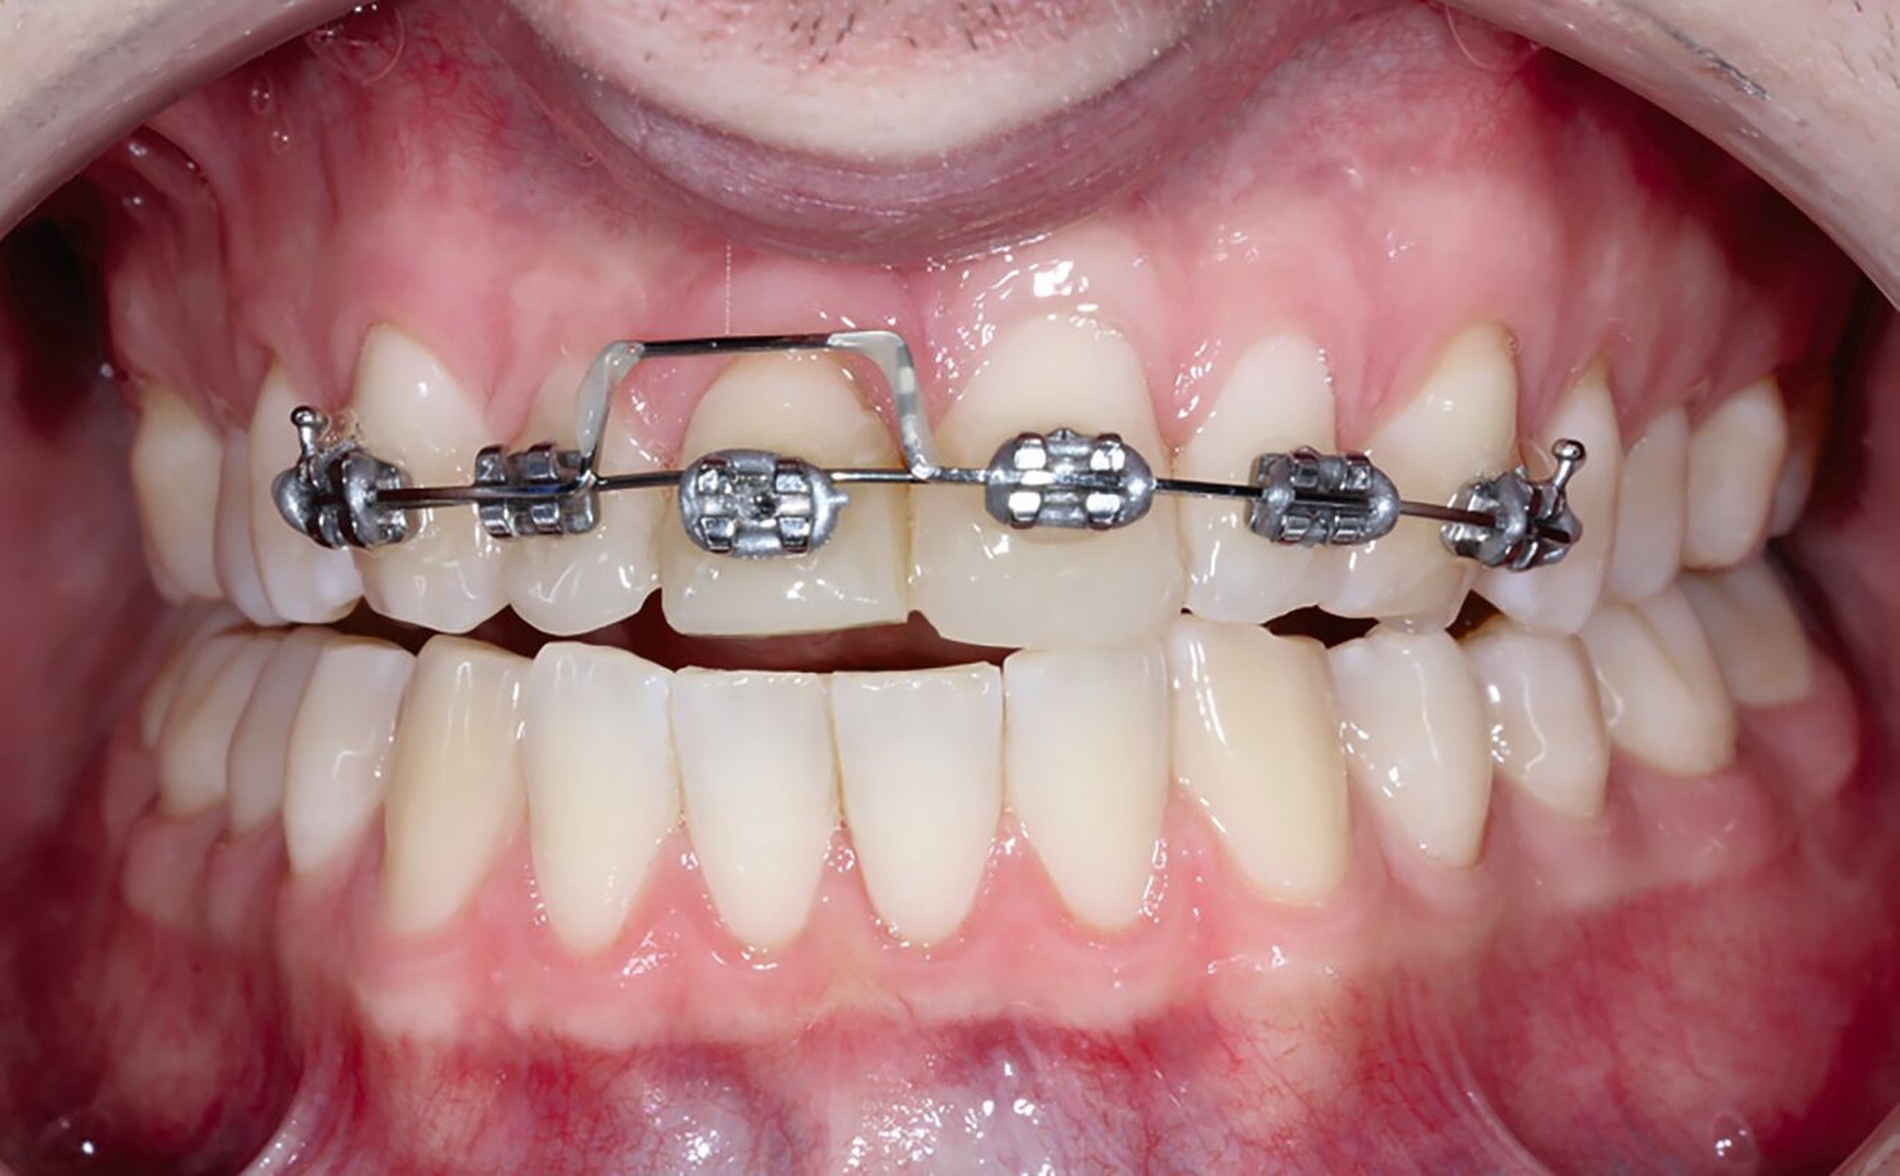

Nachfolgend konnte die Multibracket-Apparatur (MBA) für die Extrusion in Segmentbogentechnik befestigt werden (Abbildung 10). Dazu wurden die zu beklebenden Kompositflächen mit Aluminiumoxid-Pulver gestrahlt und mit einem Silan-haltigen Haftvermittler benetzt. Anschließend wurde drei Monate die kieferorthopädische Extrusionstherapie durchgeführt (Abbildungen 10 bis 12). Der Patient stellte sich wöchentlich zur Fibrotomie vor, um eine Verlagerung der Gingiva nach koronal zu vermeiden. Aufgrund der nach koronal gerichteten Bewegung erfolgte im Bedarfsfall das Einkürzen der Schneidekante.

Im Rahmen der Notfallversorgung wurden die Dentinwunden an Zahn 12 provisorisch mit Glasionomerzement verschlossen und die Zähne 11 und 21 mit Kalziumhydroxid-Präparaten direkt überkappt und anschließend dentinadhäsiv versiegelt. Im Verlauf wurde ein Wax-Up für direkte provisorische Kompositaufbauten hergestellt (Abbildung 4). Zur semipermanenten Versorgung musste per Elektrotom mesial und palatinal an Zahn 11 Gingiva exzidiert werden, um einen adäquaten Zugang und eine suffiziente Kontrolle des Arbeitsfeldes zu gewährleisten (Abbildung 5). Durch die direkte provisorische Restauration war der Patient sofort versorgt. Er konnte ohne größere Beeinträchtigung am sozialen Leben teilnehmen und hatte so Zeit für die endgültige Therapieentscheidung (Abbildungen 6 bis 8).